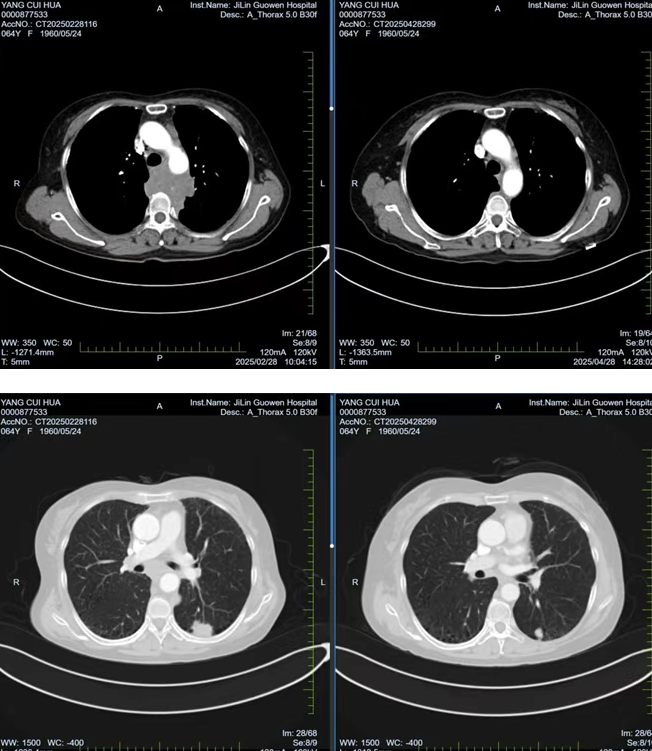

張阿姨因胸背部疼痛持續(xù) 1個月且逐漸加重,在當地醫(yī)院檢查時發(fā)現左肺存在腫物,初步考慮為惡性腫瘤。經熟人介紹,了解到我院在腫瘤專科疾病治療方面的優(yōu)勢后,該患者前往我院就診。胸部腫瘤放化療二科為其安排了 PET/CT 檢查,并對左側鎖骨上腫大淋巴結進行穿刺活檢,最終明確診斷為左肺下葉高級別神經內分泌癌,臨床分期為 cT1cN3M0 IIIb 期,且縱隔轉移淋巴結已侵犯椎體,患者因劇烈疼痛,生活質量受到嚴重影響。

經過 1 周期的免疫聯合化療后,患者的胸背部疼痛逐漸減輕,目前患者疼痛癥狀已得到改善,生活質量得到了顯著提升。